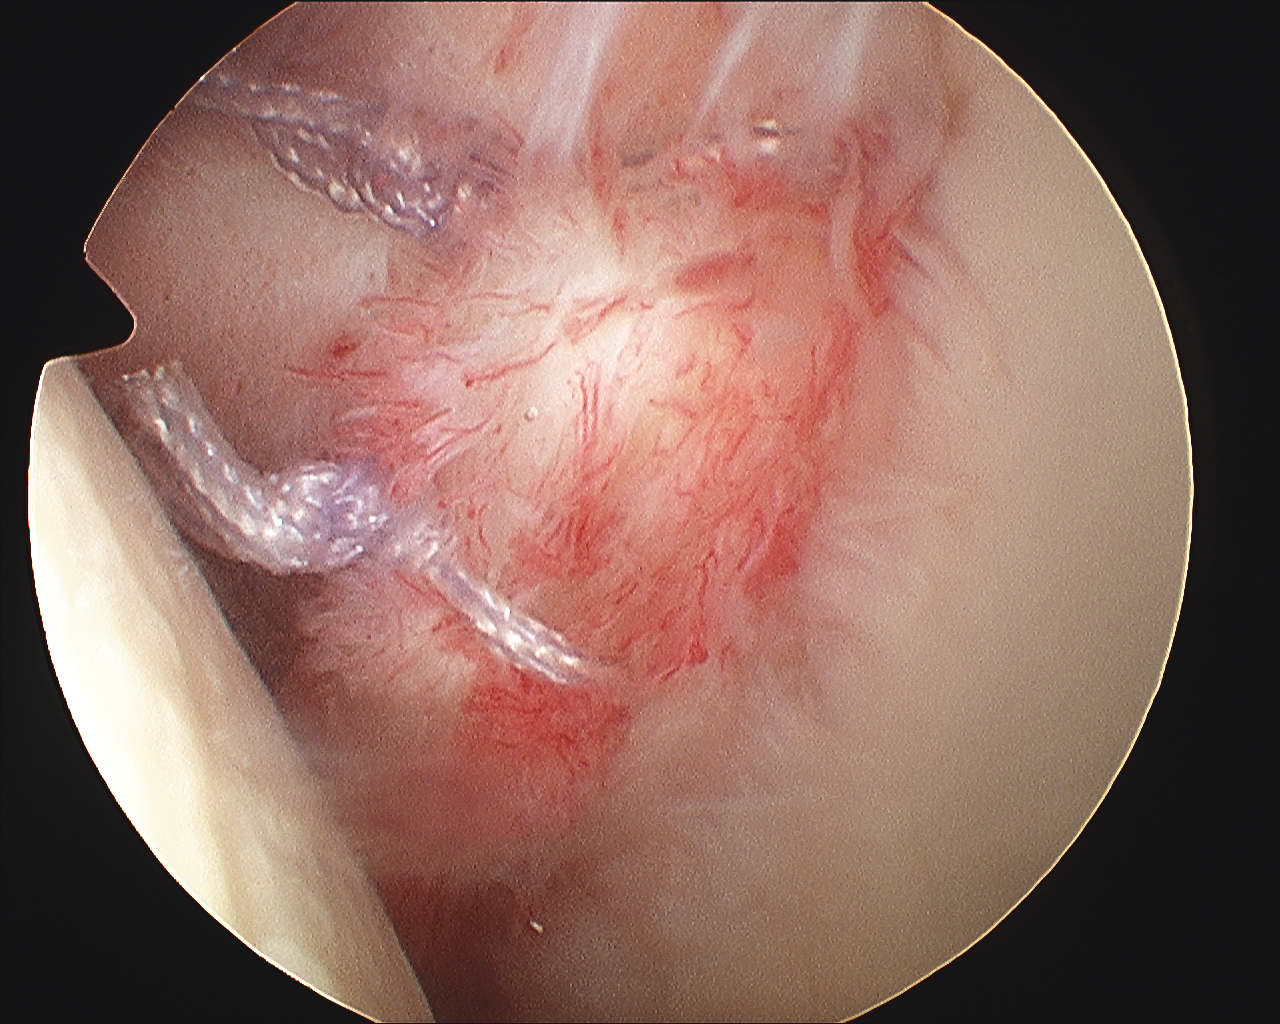

Mobilize labrum

Labral mobiliser / rasp

- labral tear can be obvious, but may have partially healed or healed medially

- change camera to anterosuperior portal for better view

- mobilize until can see subscapularis muscle underneath

- need to be able to advance labrum medially and superiorly for repair

Pass sutures and tie knots

Typically curved suture passers

Aim to tighten capsule medially and superiorly onto glenoid